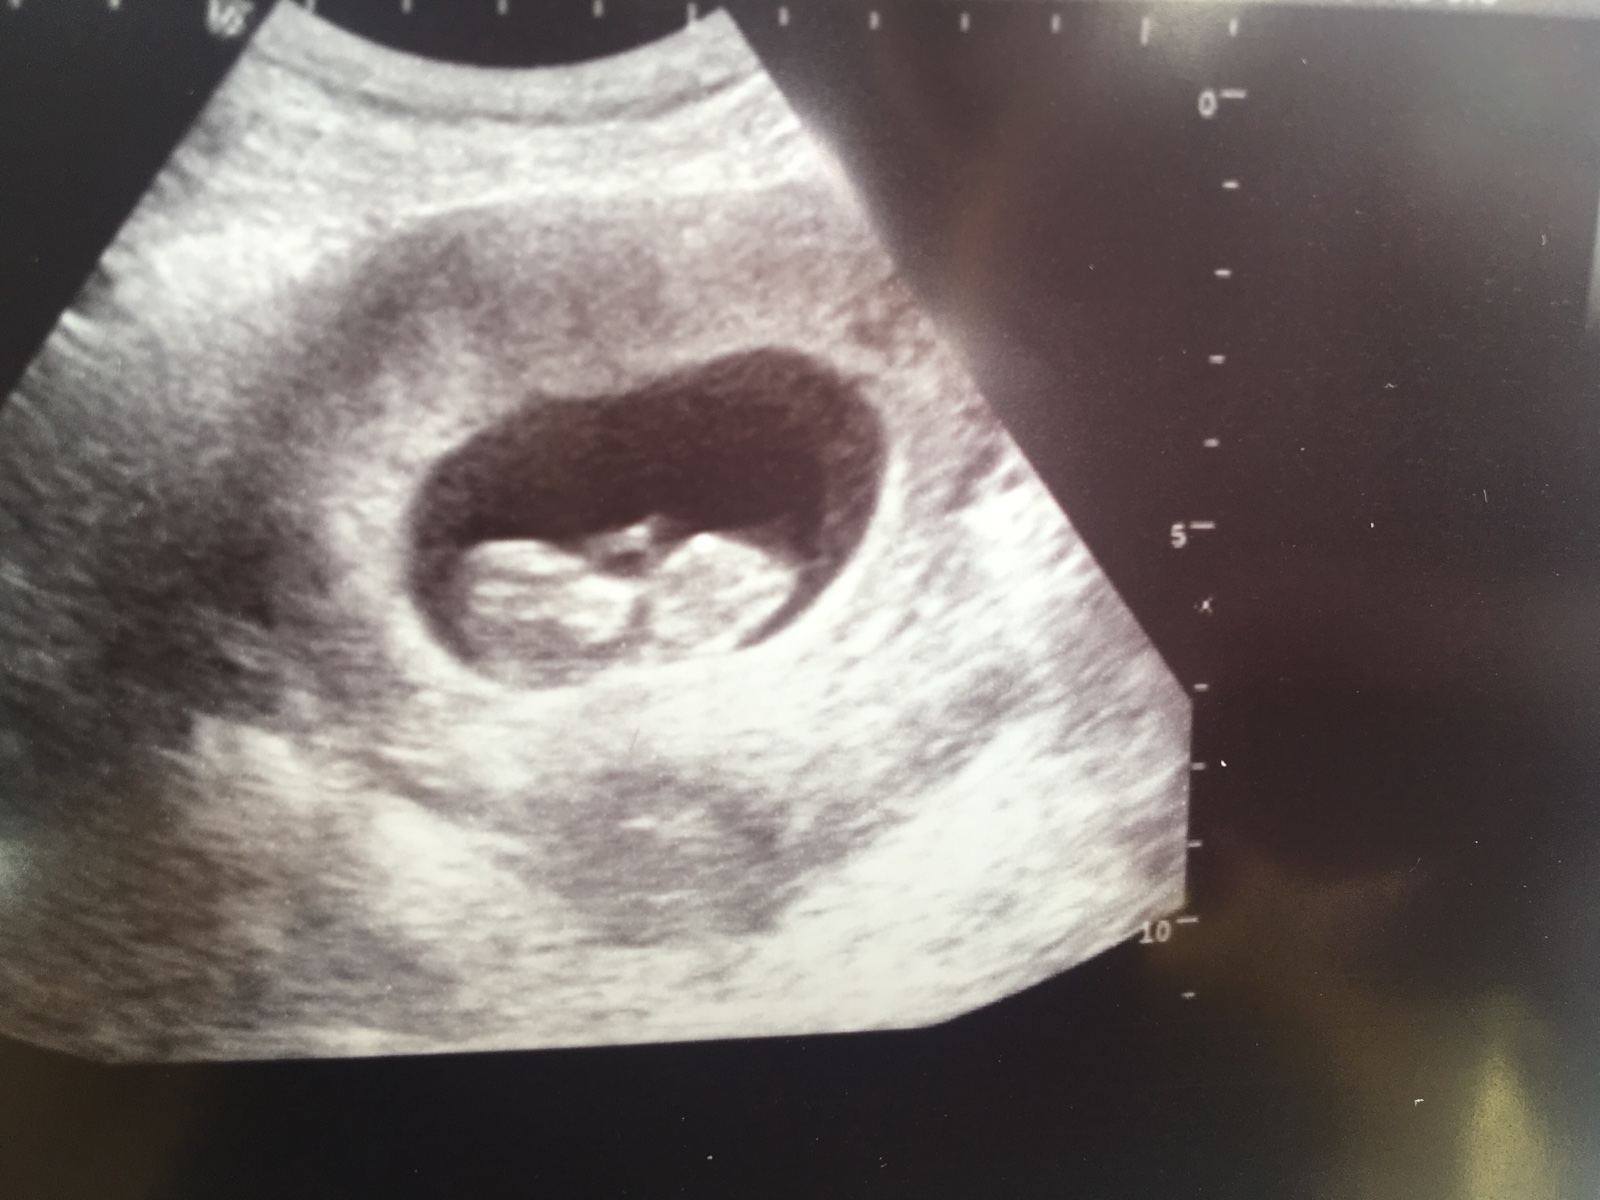

Ahoj holky já dnes 11+2,včera jsem byla na krvi v porodnici kvůli genetice,2.10 jdu na velký utz kde rovnou budou i výsledky z krve,tak držte prsty 🤗zatím mi je úplně dobře,ještě furt chodim dvakrát týdně cvičit-tabata a TRX a krásně mi to pomáhá na únavu a psychiku.Unava jinak neuvěřitelna. Všem krásný den